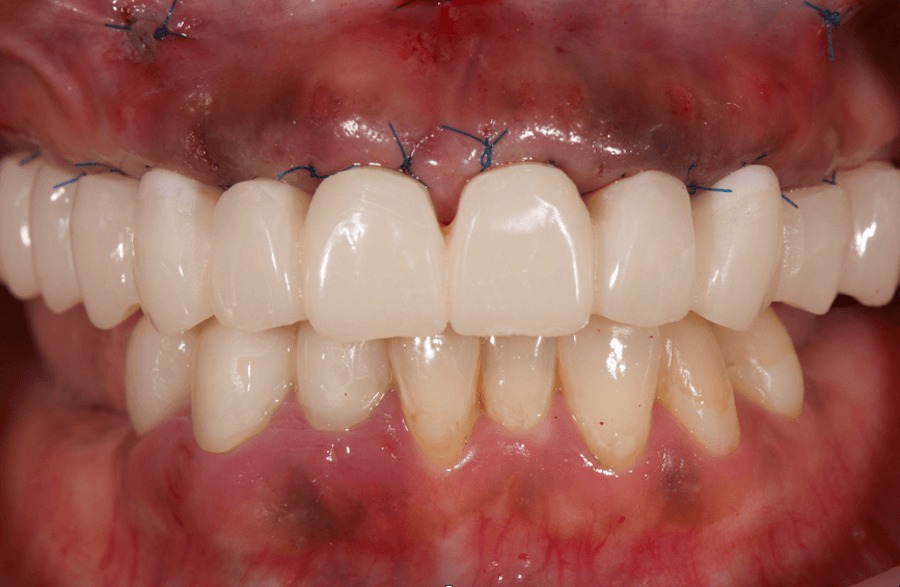

仮歯

手術と同時に、事前に用意していた仮歯をインプラントに固定

即時荷重を行い審美性と機能性を回復